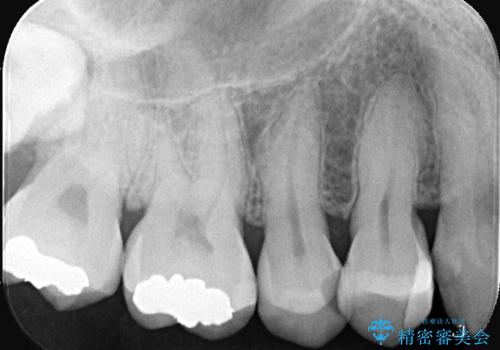

- CRの下が虫歯になっており歯が欠けている状態でした。古いCRと虫歯を除去しセラッミクインレーで治療しました。

CRが劣化し虫歯になり欠けている状態でした。歯を長持ちさせるために(再治療を減らす)セラッミクインレーで治療を行いました。

右上4のCRも劣化していてかつ形態も良くないので治療の必要性はご説明させていただきました。